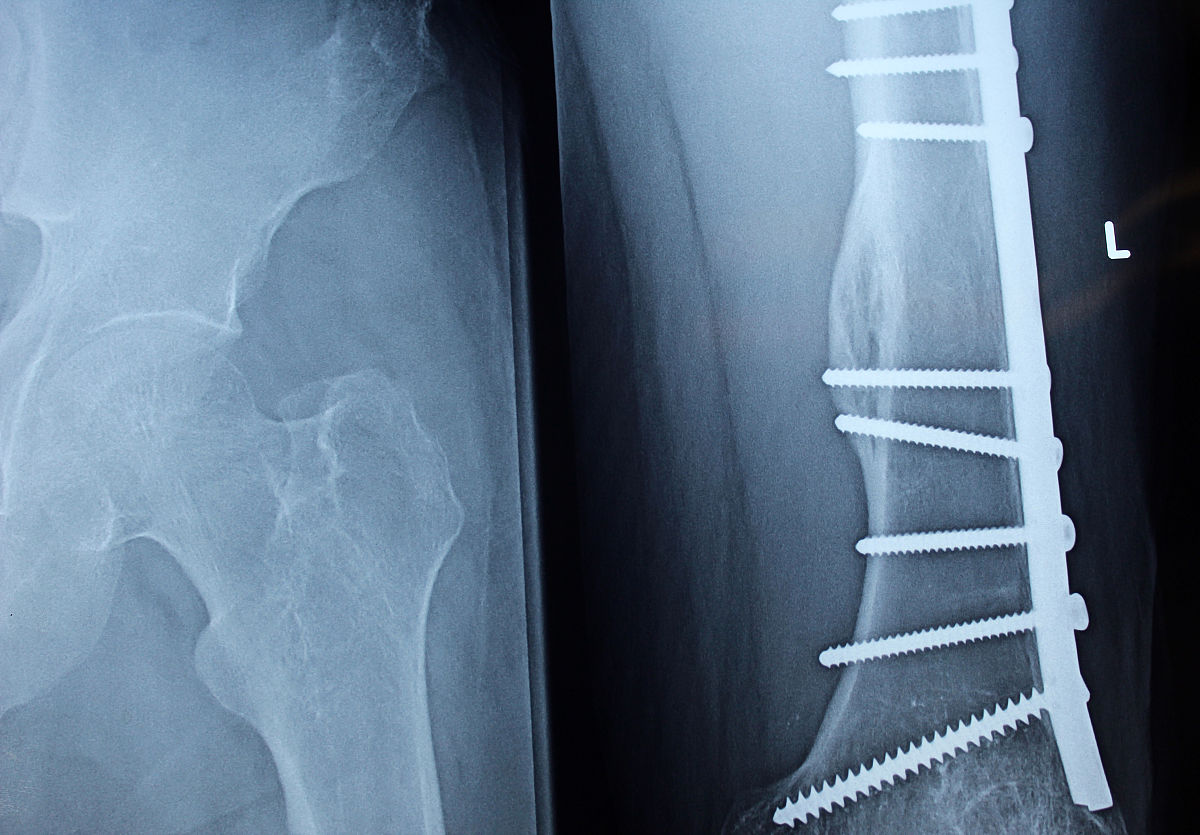

高龄股骨粗隆间骨折手术:椎管内麻醉优势及风险

高龄患者发生股骨粗隆间骨折,手术治疗是常见的选择。然而,高龄患者往往伴随其他基础疾病,麻醉方式的选择对手术安全和术后康复至关重要。与传统的全身麻醉相比,椎管内麻醉在高龄股骨粗隆间骨折手术中展现出独特的优势。